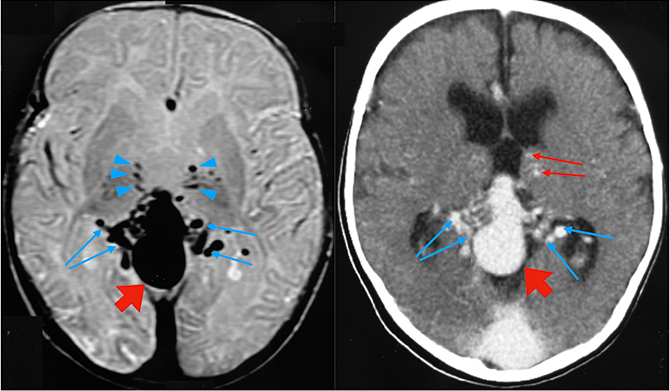

Πρώιμο σημείο απόκλισης αποτελεί η σύλληψη των μέσων εγκεφαλικών φλεβών από τους σηραγγώδεις κόλπους (cavernous sinus capture), ώστε οι οφθαλμικές φλέβες και το πτερυγοειδές πλέγμα να αρχίσουν να λειτουργούν ως εναλλακτική φλεβική και υδρική διέξοδος (κόκκινα βέλη).

Η μακροκρανία οδηγεί σε δυσωρίμανση του σκελετού της βάσεως του κρανίου με προοδευτική στένωση των σφαγιτιδικών τρημάτων και των σφαγιτιδικών βολβών (μπλέ βέλη).